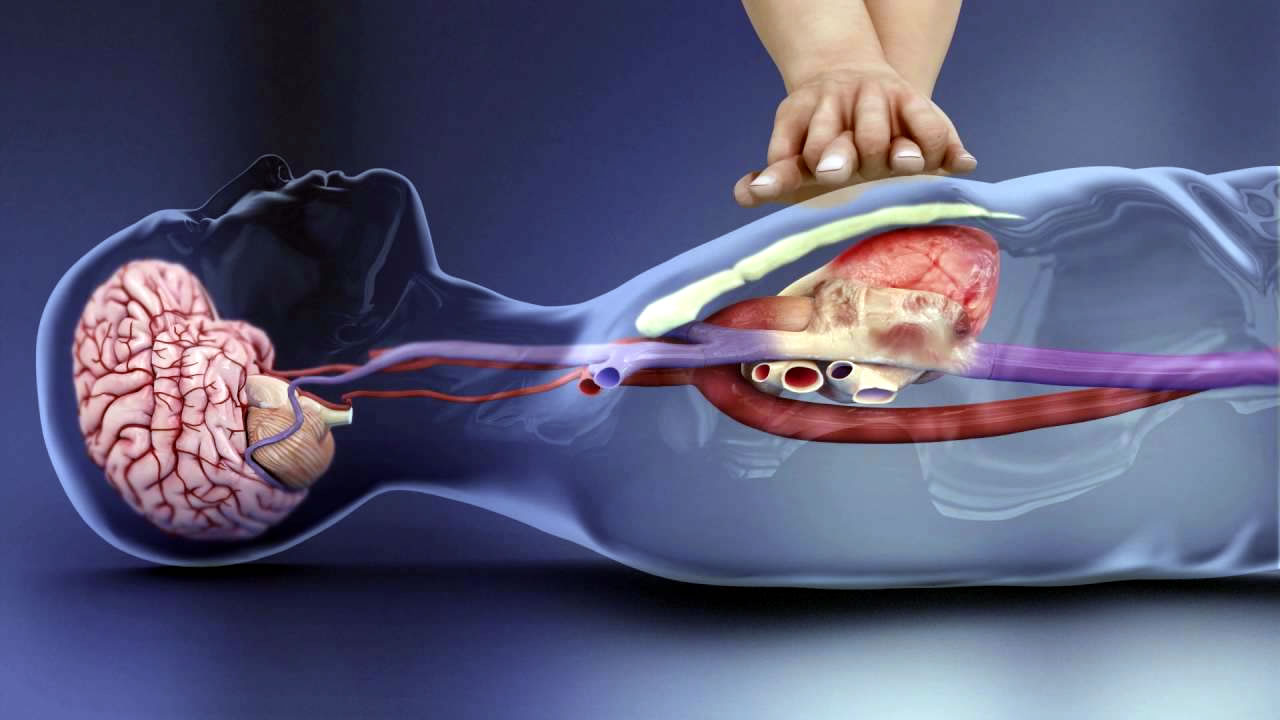

Όσοι άνθρωποι παθαίνουν καρδιακή ανακοπή στο σπίτι τους ή σε δημόσιο χώρο, δεν επιβιώνουν σύμφωνα με νέα έρευνα.

Αυτό προέκυψε από την ανάλυση των καρδιακών ανακοπών εκτός νοσοκομείου στην Αγγλία από τη Μονάδα Κλινικών Δοκιμών του Πανεπιστημίου του Warwick, η οποία διαπίστωσε ότι επιβιώνουν λιγότεροι από ένας στους 12 ασθενείς (7,8%) για 30 ημέρες.

Αυτός είναι και ο λόγος που πολίτες ζητούν να μάθουν περισσότεροι άνθρωποι τεχνικές διάσωσης και να υπάρξει μεγαλύτερη ευαισθητοποίηση για τους απινιδωτές, τις συσκευές που χορηγούν αυτόματα ηλεκτρικό ρεύμα με τη μορφή απινίδωσης (ηλεκτροσόκ) στην καρδιά για να επαναφέρουν τον κανονικό της ρυθμό μετά από ανακοπή.

Η αιφνίδια καρδιακή ανακοπή είναι η άμεση απώλεια κάθε καρδιακής δραστηριότητας λόγω ακανόνιστου καρδιακού ρυθμού. Η αναπνοή σταματά και το άτομο χάνει τις αισθήσεις του.

Η άμεση αντιμετώπιση, μέσω της καρδιοπνευμονικής αναζωογόνησης (ΚΑΡΠΑ) ή τη χρήση απινιδωτή, μπορεί να επαναφέρει τους ανθρώπους, αλλά οι περισσότεροι τελικά πεθαίνουν.

Τα νέα δεδομένα για το 2022, που βασίζονται σε στοιχεία από όλες τις υπηρεσίες ασθενοφόρων της Αγγλίας, έδειξαν ότι πραγματοποίησαν ανάνηψη σε 34.407 ασθενείς μετά από καρδιακή ανακοπή εκτός νοσοκομείου.

Τα δύο τρίτα των καρδιακών ανακοπών συνέβησαν σε άνδρες, περίπου το 80% συνέβησαν στα σπίτια των ανθρώπων και το 13% σε δημόσιο χώρο, ενώ ο μέσος όρος ηλικίας των ασθενών ήταν τα 65 έτη.

Στο 25% των ασθενών η καρδιά επανεκκινήθηκε μέχρι να φτάσουν στο νοσοκομείο, αλλά λιγότεροι από ένας επέζησαν ένα μήνα, γεγονός που δείχνει μικρή πτώση σε σχέση με τα στοιχεία του 2021.

Πολίτες έκαναν καρδιοπνευμονική αναζωογόνηση σε περισσότερο από το 70% των περιπτώσεων, αλλά χρησιμοποίησαν απινιδωτή δημόσιας πρόσβασης σε λιγότερες από μία στις 10 περιπτώσεις. Και τα δύο στοιχεία δείχνουν αύξηση σε σχέση με το 2021.

Το Μητρώο Αποτελεσμάτων Καρδιακής Ανακοπής εκτός Νοσοκομείου, από το οποίο αντλούνται τα δεδομένα, χρηματοδοτείται από το Βρετανικό Συμβούλιο Αναζωογόνησης (RCUK) και το Βρετανικό Καρδιολογικό Ίδρυμα (BHF).

Ο Δρ. Christopher Smith, λέκτορας στην Ιατρική Σχολή του Warwick και συν-επικεφαλής ερευνητής, δήλωσε ότι τα στοιχεία δείχνουν ότι τα ποσοστά επιβίωσης παραμένουν χαμηλά.

«Η καρδιακή ανακοπή είναι το πιο σοβαρό και κρίσιμο ιατρικό επείγον περιστατικό, αλλά μπορούν να γίνουν πολλά για να βελτιωθούν τα στοιχεία. Ειδικότερα, υπάρχει ανάγκη για καλύτερο συντονισμό και εφαρμογή παρεμβάσεων με βάση την κοινότητα, όπως η ΚΑΡΠΑ από τους παρευρισκόμενους και η χρήση απινιδωτών δημόσιας πρόσβασης» είπε.

Ο James Cant, διευθύνων σύμβουλος του Συμβουλίου Αναζωογόνησης του Ηνωμένου Βασιλείου, δήλωσε: «Θέλουμε να σώσουμε περισσότερες ζωές και να μειώσουμε τις καταστροφικές συνέπειες της καρδιακής ανακοπής για τους ασθενείς και τις οικογένειές τους. Η έκθεση ρίχνει φως στις τάσεις επιβίωσης, ΚΑΡΠΑ και απινιδωτών, επιτρέποντάς μας να εφαρμόσουμε μια προσέγγιση βασισμένη στα δεδομένα για να σώσουμε περισσότερες ζωές».

Η Judy O’Sullivan, διευθύντρια προγραμμάτων καινοτομίας στον τομέα της υγείας στο BHF, δήλωσε: «Κάθε δευτερόλεπτο είναι ζωτικής σημασίας όταν κάποιος παθαίνει καρδιακή ανακοπή. Η γρήγορη ΚΑΡΠΑ και απινίδωση μπορεί να κάνει τη διαφορά μεταξύ ζωής και θανάτου. Τα στοιχεία αυτά αποκαλύπτουν τα ανησυχητικά χαμηλά ποσοστά επιβίωσης μετά από καρδιακή ανακοπή εκτός νοσοκομείου και δείχνουν ότι χάνονται πάρα πολλές ευκαιρίες για να βοηθηθεί η διάσωση μιας ζωής. Πρέπει να το αλλάξουμε αυτό. Είναι σημαντικό να έχουμε αυτοπεποίθηση, να κάνουμε ΚΑΡΠΑ και να χρησιμοποιούμε απινιδωτή. Το δωρεάν, διαδραστικό εκπαιδευτικό εργαλείο RevivR μπορεί να σας διδάξει τη σωτήρια δεξιότητα της ΚΑΡΠΑ και τη χρήση απινιδωτή σε μόλις 15 λεπτά και θα μπορούσε τελικά να βοηθήσει να σωθεί η ζωή ενός αγαπημένου σας προσώπου».